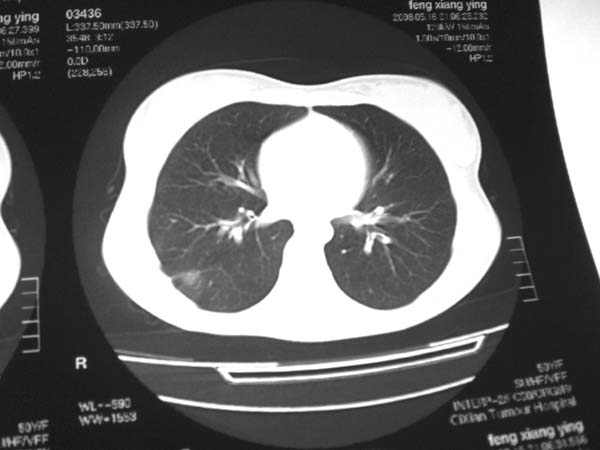

标题: CT13486:F 17Y 咳嗽 咳痰数日请会诊 [打印本页]

标题: CT13486:F 17Y 咳嗽 咳痰数日请会诊

白细胞9600不发烧

考虑右下结核球

右肺下叶结核灶

右下肺背段病灶,考虑结核与炎症鉴别,请进一步检查.

考虑为:右肺下叶外基底段结核球。

结果;痰中找到结核杆菌

痰涂片已找到结核杆菌  将结果告诉大家